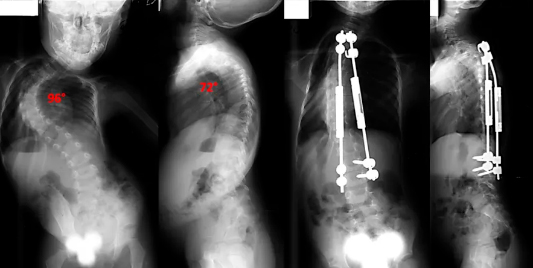

Correção de escoliose “S” idiopática dupla-curva